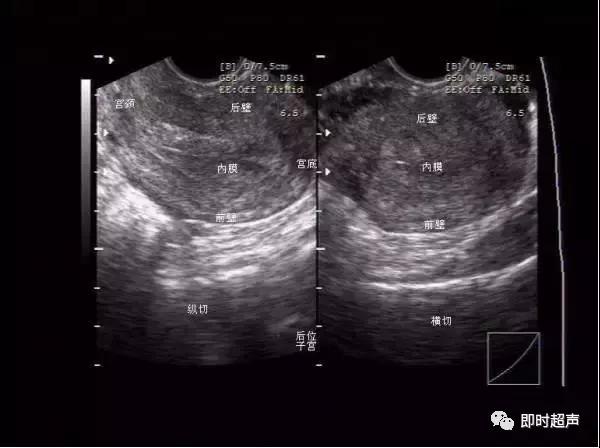

图像方位的确认

阴式超声探头位置示意图